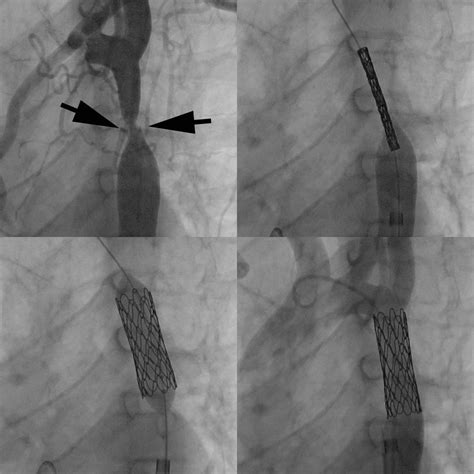

• Imaging: Contrast dye may be injected through the catheter to visualize the heart's structure and blood flow using fluoroscopy or other imaging techniques.

• Interventions: In some cases, interventions such as balloon valvuloplasty or stent placement may be performed during the procedure to treat specific heart conditions.

• Improved Imaging: Advanced imaging techniques, such as intravascular ultrasound and optical coherence tomography, provide detailed visualizations of the heart's structure and blood vessels.

• Interventional Procedures: Advances in interventional techniques, such as balloon valvuloplasty and stent placement, enable cardiologists to perform complex procedures during the catheterization.